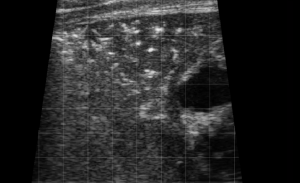

SIMON Ultrasound Database

This ultrasound database is a free resource for students and doctors!

Our collection includes videos of dogs, cats, horses, cows, humans, and many other species!